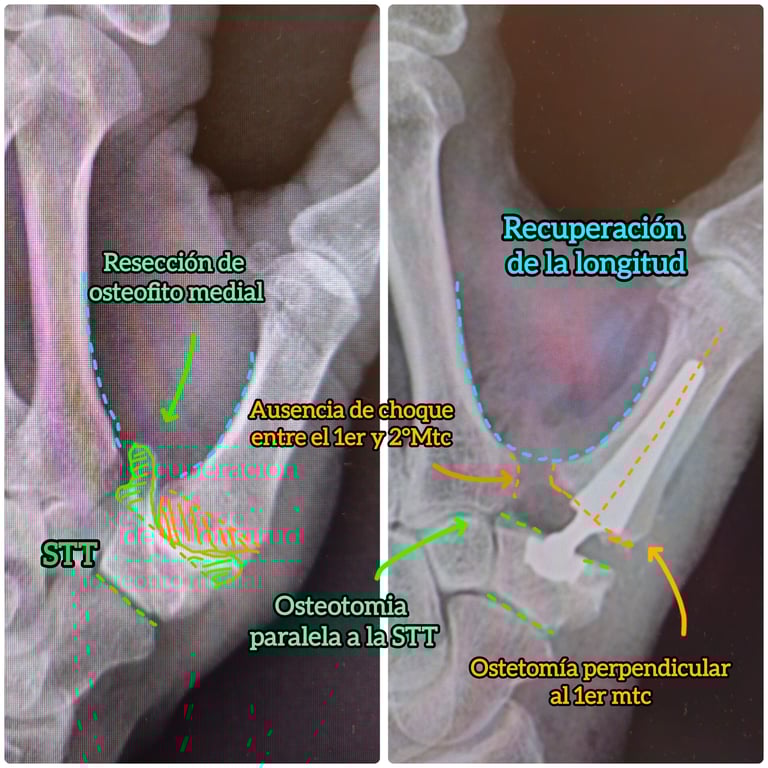

A través de pequeñas incisiones y bajo visualización artroscópica, se reseca únicamente la porción patológica del trapecio, conservando la estabilidad y la biomecánica del pulgar. Esta técnica permite un menor dolor postoperatorio, movilización precoz y una recuperación funcional más rápida en comparación con técnicas abiertas más agresivas.

Estabilidad definitiva para casos avanzados

La artrodesis trapeciometacarpiana por artroscopia permite tratar la rizartrosis avanzada mediante la fusión controlada de la articulación, preservando la biomecánica del pulgar y reduciendo el dolor de forma definitiva. La asistencia artroscópica facilita una preparación precisa de las superficies articulares y una mínima agresión tisular, mientras que los tornillos canulados cruzados aportan una fijación sólida y fiable.